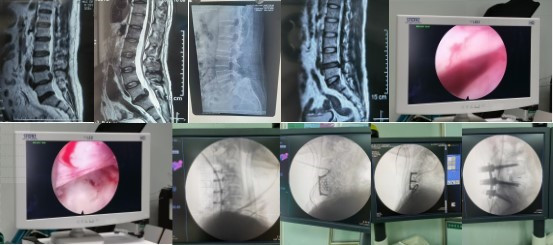

由于椎间盘高度游离及肥胖等因素该手术难度高,杨宝辉副主任医师面对挑战迎难而上,考虑到患者较为年轻,为患者制订个体化手术方案:即脊柱内镜下髓核摘除术,该手术切口仅仅8mm左右,对肌肉及骨骼破坏极少,但同时对手术技术要求较高。于10月15日,患者按既定的手术方案如期进行,但在术中发现患者背部及脂肪及肌肉非常厚,导致工作套管几乎全部陷入,无法有效摆动等问题,杨宝辉副主任医师通过自制的工作套管克服该困难,同时由于髓核向上高度游离,且突出节段在腰4-5部位,该部位椎板间隙狭窄,在缺乏镜下环锯等困难下,杨宝辉副主任医师通过调整工作套管,应用磨钻对上位椎板小心翼翼的磨除进入椎管。由于患者椎管内脂肪组织丰富导致神经结构不清,杨宝辉副主任医师充分暴露出神经根及硬膜囊,凭借丰富的手术经验终于掏出了一大块游离的髓核组织,台下医护看到这一幕露出了敬佩的表情,也标志着手术的圆满成功。该手术历时2小时,术后患者症状立竿见影,第二天就佩戴腰围开始床下活动。维吾尔族小伙子在杨教授查房时激动滴说“谢谢杨教授治好了我的腰!”。

在过去的一周内,杨宝辉副主任医师已经完成4例类似的高难度游离型椎间盘突出。自入疆以来,他还开展了科室首例经多裂肌肉间隙入路治疗胸腰椎骨折术;在缺乏器械的情况下,完成科室首例Wiltse入路改良的腰椎TLIF手术;自制工作套管完成多例侧入路椎间孔镜手术;在常规开展手术的基础上,完成高难度肥胖患者的腰椎3度滑脱、氟骨症患者多节段腰椎管狭窄症、上胸段结核的病灶清除植骨融合内固定术,颈脊髓损伤的前后路手术等高难度手术。